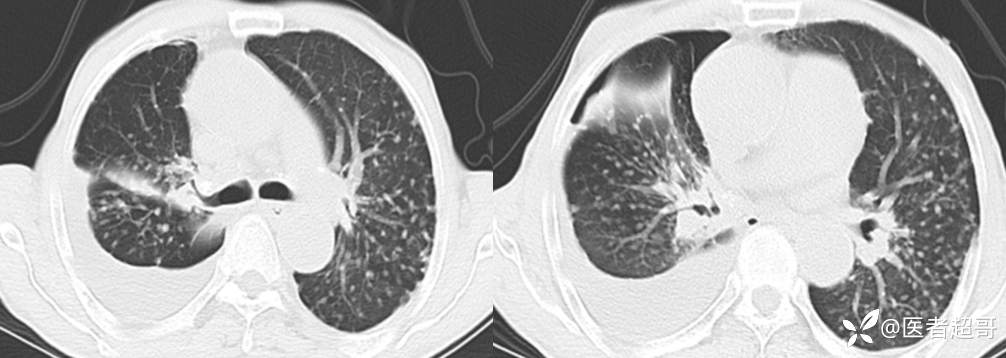

患者,男,72岁,农民,于2021年05月26日17时20分因"发作性精神行为异常10+天"入院。@丁香影像频道

肺炎支原体肺炎 (105)